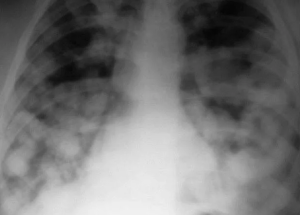

Трудности диагностики метастатического поражения легких

Рентгенологические признаки изменений в легких не соответствовали обычным характеристикам метастатического поражения при РМЖ и имитировали течение пневмонии без ответа на антибактериальную терапию